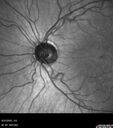

Optic Disc Drusen in a child (non Calcified)33 viewsFluorescein angiography shows no leakage

Optic Disc Drusen in a child (non Calcified)28 viewsFluorescein angiography shows no leakage

Optic Disc Drusen in a child (non Calcified)27 viewsFluorescein angiography shows no leakage

Optic Disc Drusen in a child (non Calcified)26 viewsFluorescein angiography shows no leakage

Optic Disc Drusen in a child (non Calcified)25 viewsFluorescein angiography shows no leakage

Optic Disc Drusen in a child (non Calcified)24 viewsFluorescein angiography shows no leakage

Optic Disc Drusen in a child (non Calcified)23 viewsFluorescein angiography shows no leakage

Optic Disc Drusen in a child (non Calcified)21 viewsFluorescein angiography shows no leakage